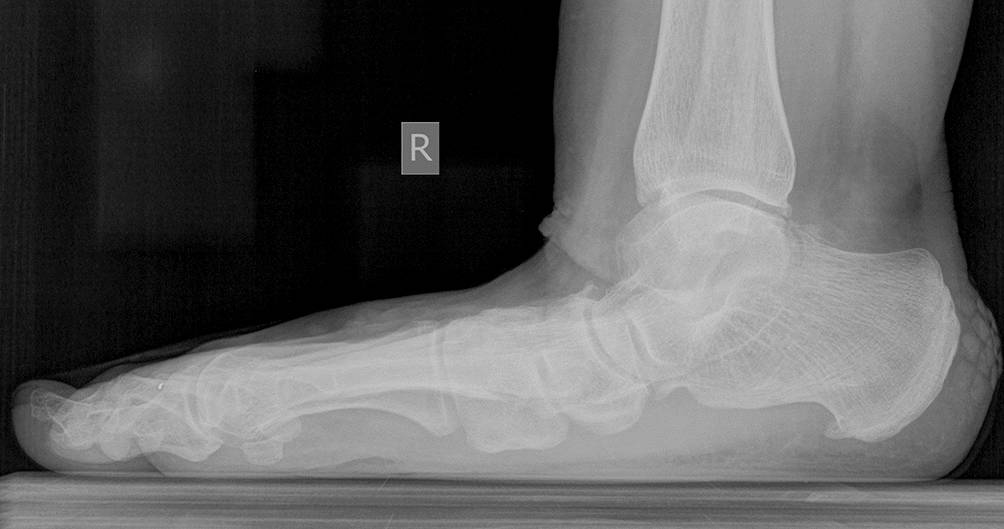

Abb. 4

Zusammenbruch des Längsgewölbes unter Belastung, aktiv dekompensiert. © C. Biehl

In den mittleren Stadien (LDE 2–3, Johnson und Strom II) gehören neben der Fußbettung und der bereits hier schon erforderlichen Schuhversorgung bereits operative Versorgungen an den Gelenken zur Therapie. Bei nicht mehr funktionell suffizienter Versorgung der medialen Stabilisatoren ist letztlich eine frühzeitige talonavikulare Arthrodese erforderlich (Abb. 4) und eine Tibialis-posterior-Augmentation nicht mehr ausreichend, um das Gelenk und die Kinematik der gesamten Extremität zu halten. An den Zehen reichen Sehnenverlängerungen nicht aus, um Druckstellen und Ulzera zu vermeiden. Indiziert sind Korrekturosteotomien der Metatarsalia und Arthrodesen an den Phalangen.